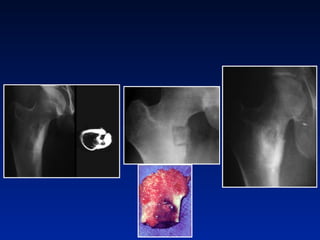

Tratamento cirurgico clássico

Tratamento cirurgico exerese de nicho Nicho em colo femural

Tratamento cirúrgico Mulher 19 anos